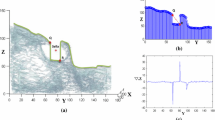

The procedure involves an adaptive cluster-based segmentation of bone tissues followed by an intensity-based registration of an annotated reference volume onto a patient Cone Beam CT (CBCT) head volume. The outcomes of the annotation process are presented to the clinician as a 3D surface of the patient skull with the estimate landmark displayed on it. Moreover, each landmark is centered into a spherical confidence region that can help the clinician in a subsequent manual refinement of the annotation. The algorithm was validated onto 18 CBCT images.

Automatic segmentation shows a high accuracy level with no significant difference between automatically and manually determined threshold values. The overall median value of the localization error was equal to 1.99 mm with an interquartile range (IQR) of 1.22–2.89 mm.